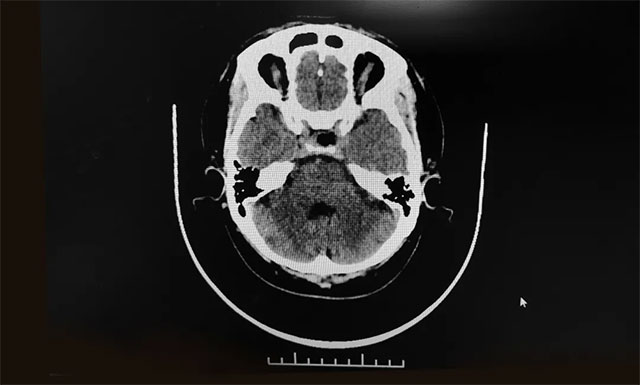

目前的影像学检查对早期确诊垂体瘤有重要意义,如怀疑为垂体瘤,通常经过正规医院的磁共振检查和CT 扫描,就可以及时把垂体瘤这个“元凶”揪出来。

▲ 术后影像显示肿瘤被切除